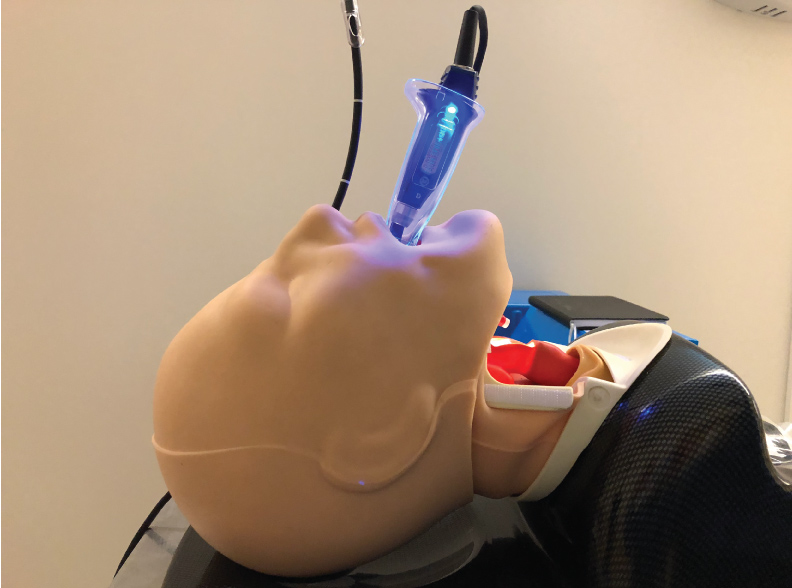

This combined technique of using the VL in combination with the FIS is also of great use when intubation has to be performed awake. Visualizing the vocal cords with the VL in an awake patient much better tolerated than with a conventional DL. With the VL there is no need to apply force to the vallecula to obtain a view of the vocal cords. So, it is much less likely to make the patient gag or precipitate laryngospasm. This also makes the VL an opportune intubation aid when endotracheal intubation has to be performed in the absence of neuromuscular blocking agents. Low profile blades for VLs are now available. They have been designed for use in patients with limited mouth opening. The low-profile blades allow a VL blade to be inserted into the patient's mouth as long as mouth opening is wide enough for the ETT to pass (Figure 8). These airway management techniques can also be used in children and low profile VL blades can be used even in small children. The availability of low profile VL blades now relegates the conventional FIS intubation to cases where there is absolutely no mouth opening. The most common scenario of this is when the mandible has been wired to the maxilla.

Figure 8: Low profile video-laryngoscope (VL) blade for use with limited mouth opening.